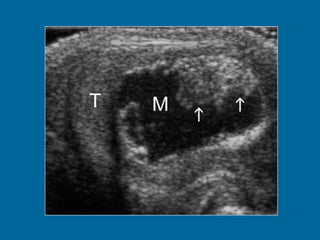

Tumor del senoendodermico mass. (a) Longitudinal US scan of the left hemiscrotum shows a solid tumor (T) replacing the entire testis. The cystic areas (arrowheads) represent tumor necrosis.

C A RC I N O M A D E C E L U L A S E M B R I O N A R I A S Generalidades Segunda neoplasia germinal más frecuente. Pico de incidencia entre la segunda y tercera década de vida. A menudo mixto. Mayor agresividad que el seminoma. Poco quimio y radiosensibles con altos niveles de AFP. Forma infantil, tumor del seno endodérmico o saco vitelino.

Ecografía Masa onódulo Pequeño. Ecoestructura heterogénea. Hipoecogénico. Márgenes mal delimitados. Degeneración quística. Focos ecogénicos con o sin sombra acústica.